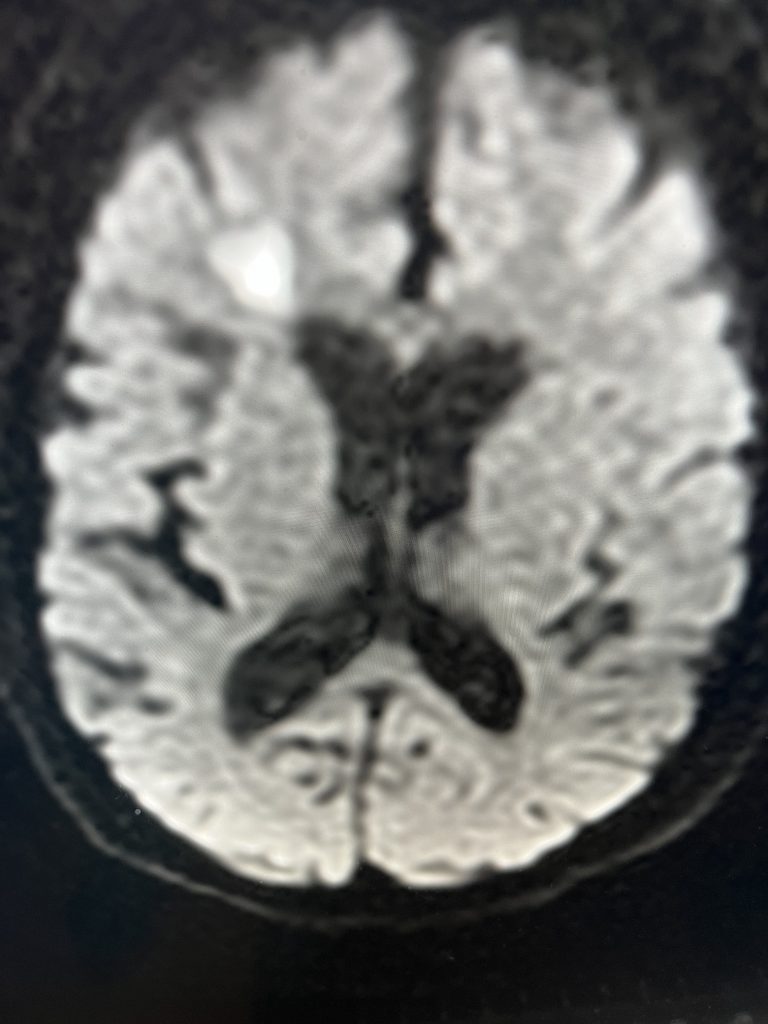

Brain:

Cerebral Metastases from Non-Small Cell Lung Cancer

Author: Xavier P. J. Gaudin D.O., F.A.C.O.S., Read More!